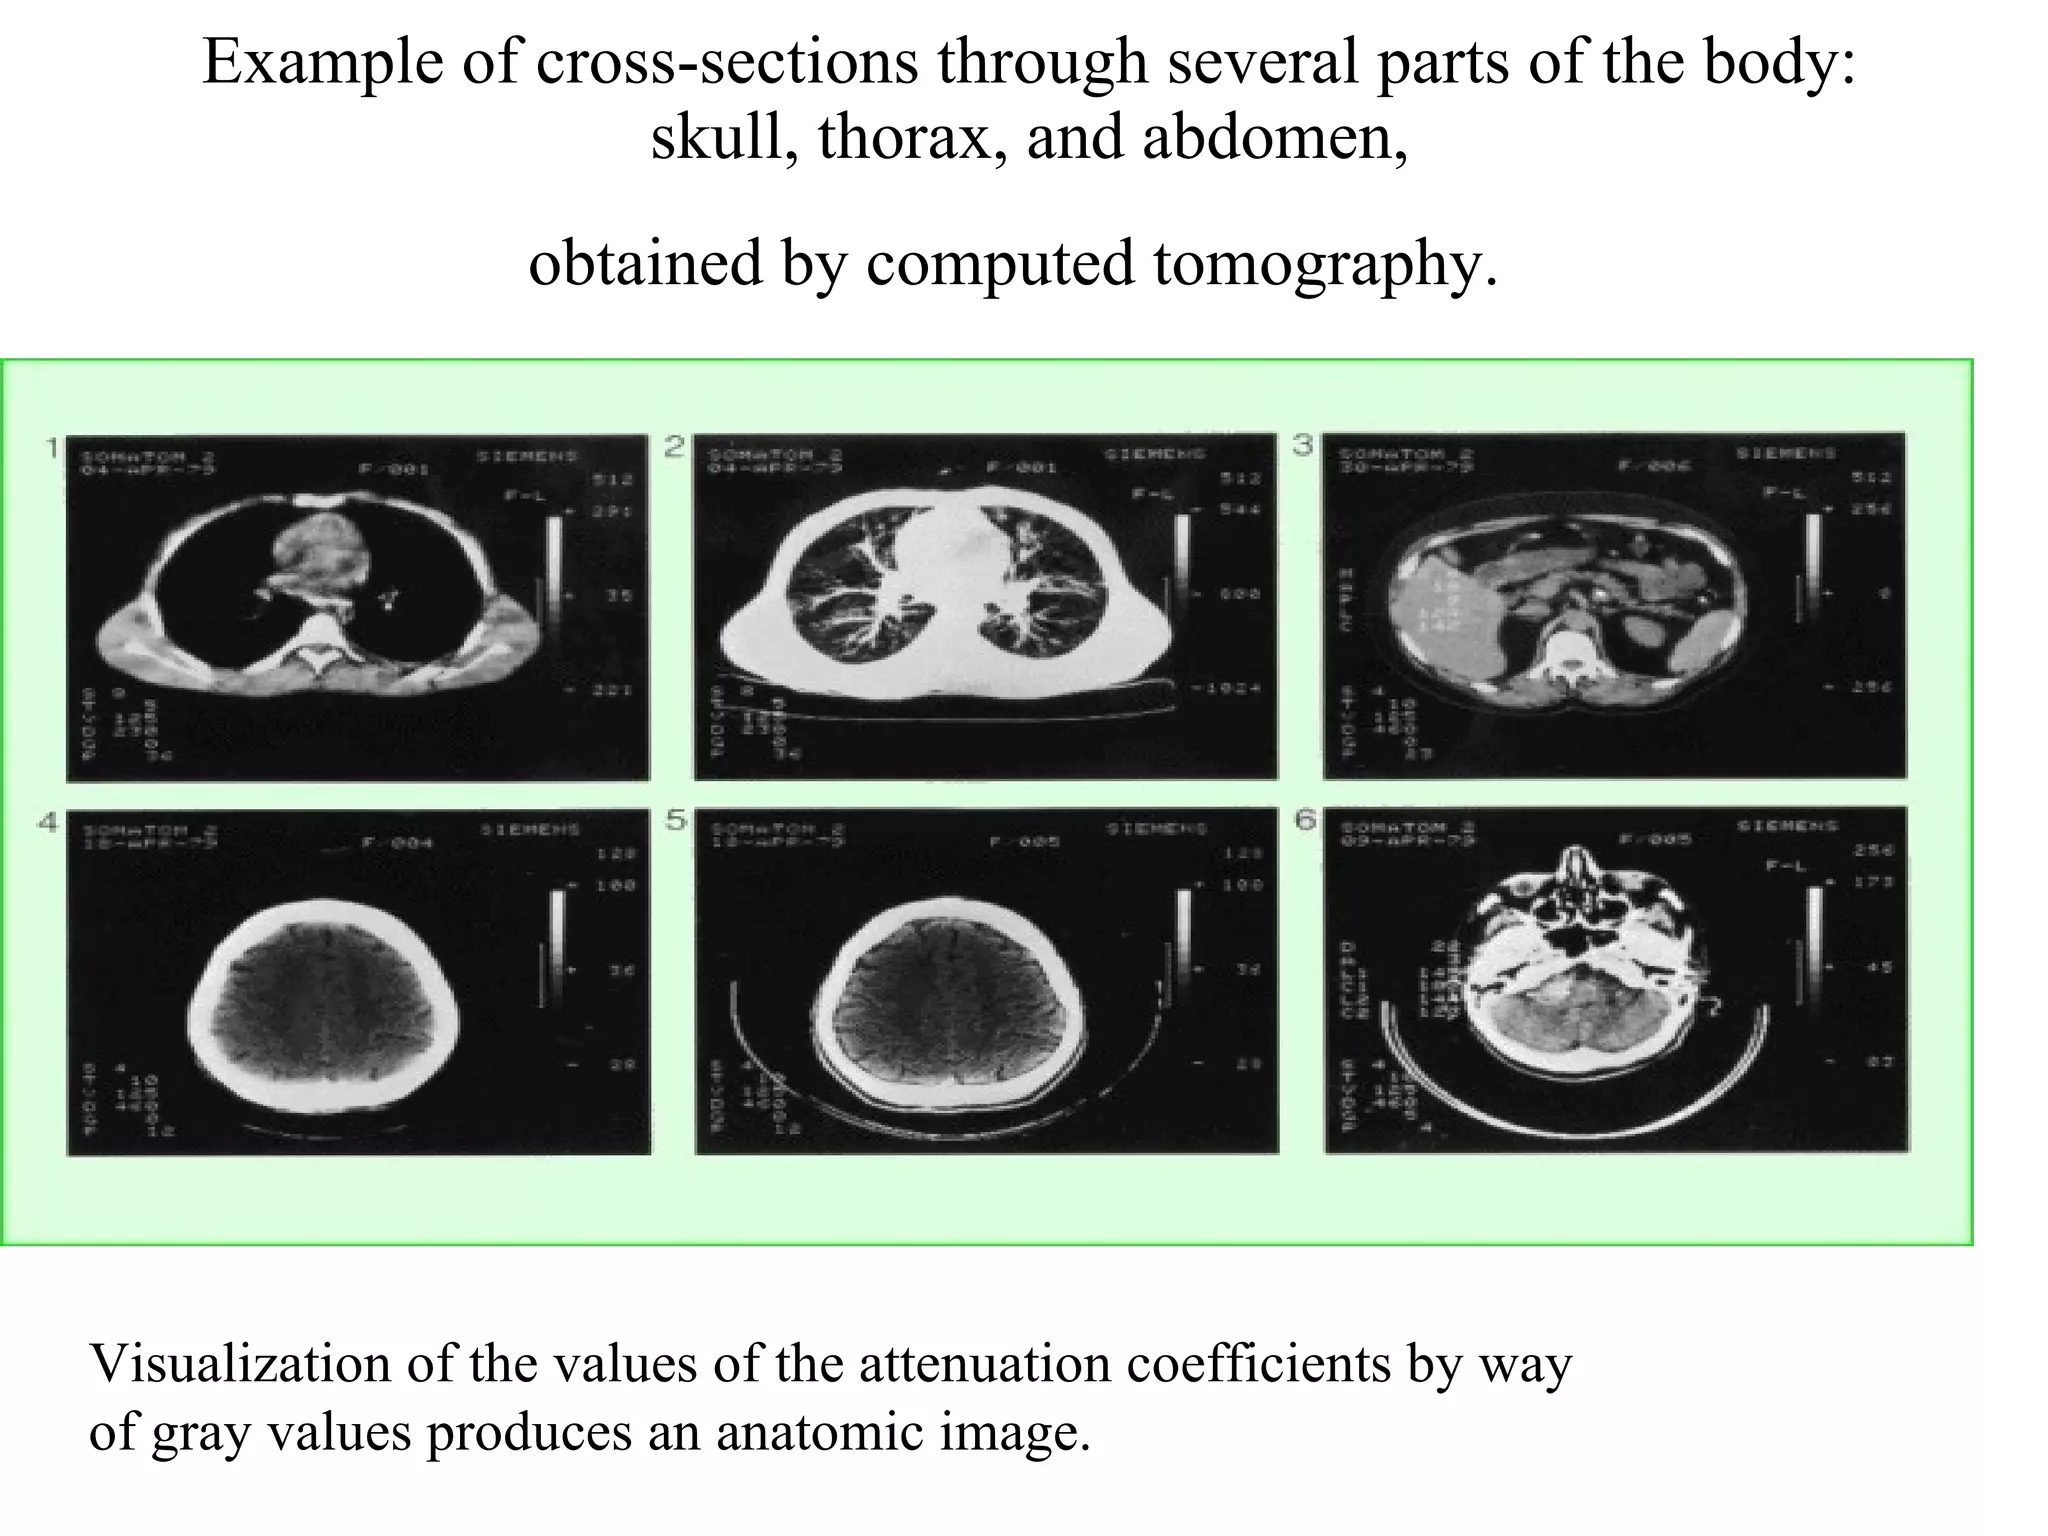

The document discusses various medical imaging modalities including x-rays, computed tomography (CT), and digital mammography. It describes the basic principles and historical development of these technologies, how images are formed, and what types of anatomical features and abnormalities they can detect. Key advances include the development of digital systems that allow image manipulation and remote consultation. While promising, digital mammography still faces challenges around resolution and cost.